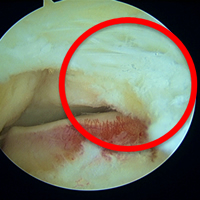

保存療法では痛みが取れない場合には、手術療法が選択されます。手術では主に内視鏡を使用して三角骨の摘出、並びに長母趾屈筋腱の腱鞘の切開を行っています。

内視鏡の手術では腹臥位(うつ伏せ)で行います。アキレス腱の両側に7mm程度の傷をつけるだけで手術を行うことができます。手術中に足関節後方の滑膜炎の程度(痛み具合)や長母趾屈筋腱の障害の程度を評価し、お一人おひとりの状態に合わせたリハビリを行っていきます。